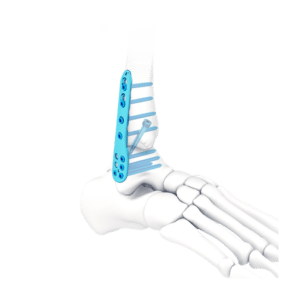

CLAVO PARA ARTRODESIS DE TOBILLO

El clavo para artrodesis de tobillo está diseñado para deformidades y artritis graves del pie y el tobillo.